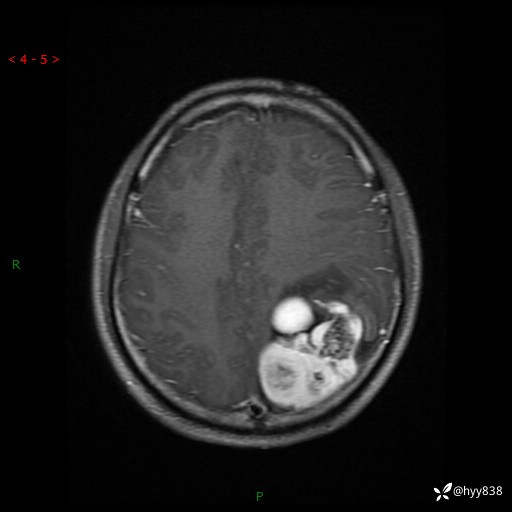

性别:男

年龄:21岁

简要病史:头痛伴呕吐半年,渐进性加重1月

颅脑MRI平扫+增强